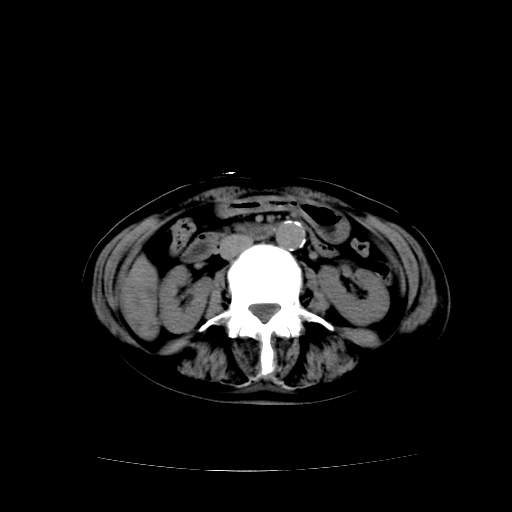

女70y乳腺ca(针吸活检)

多部位转移瘤的诊断可以肯定,我的疑问是:双肺对称高密度影及胸水是否为心衰肺水肿,病人体虚弱,不好意思图象传的乱![em9]

1)左侧乳腺癌并左侧腋窝及纵隔淋巴结转移,两肺淋巴道转移(癌性淋巴管炎),肝脏多发性转移。2)双侧胸腔积液。3)慢性胆囊炎。

2、左腋窝、纵隔淋巴结肿大(转移性);

1)左侧乳腺癌并左侧腋窝及纵隔淋巴结转移,肝脏多发性转移。2)双侧胸腔积液伴双肺蝶翼样磨玻璃高密度影,双侧肺门血管影增粗(图像不全,肺门层面没纵隔窗),考虑心功能不全所致。3)慢性胆囊炎伴壁钙化。